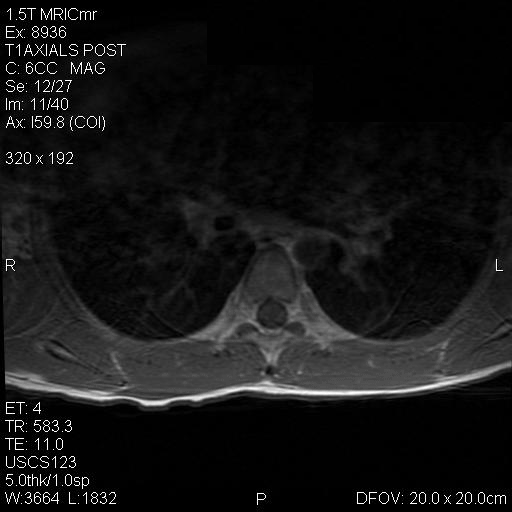

Panel A to E are MR images. Panel F and G are taken from intraoperative cytologic preparation. Panel H to M are taken from frozen section. Panel N and O are from paraffin section. These sections are stained by hematoxylin-eosin stain. Panel P is immunohistochemistry for neurofilament proteins. Panel Q is stained by Luxol fast blue-Periodic acid Schiff (LFB-PAS) stain.

The segment of spinal cord at T3-T4 level is expanded and is accompanied by edema that runs from T2-T6. The expansion and edema is roughly symmetrical along the long axis of the cord. The expanded levels are isointense to the white matter of the spinal cord on T1-weighed images (Panel A). The edema is best demonstrated on T-weighed images (Panel B, C, and E). Patchy and poorly defined enhancement is demonstrated in the expanded areas (Panel D). The remaining levels of the spinal cord and the brain are free of abnormal changes.